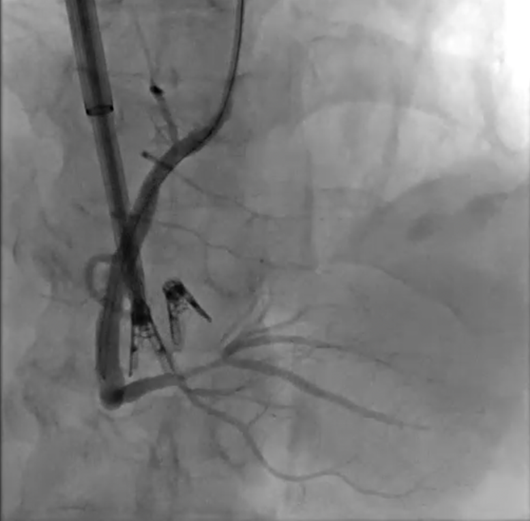

经过充分的术前准备,手术在浑南院区介入手术室如期进行。首先,团队在超声引导下穿刺右侧颈内静脉成功,送18F大鞘入右房,应用三尖瓣环修复系统,调整夹合器至三尖瓣后叶-隔叶交界区瓣环处,旋入定位器,同时行右冠脉造影,根据结果调整夹子位置,确保右冠脉血流不受明显影响,释放夹合器,超声示瓣环面积缩小,反流减轻。再将另一枚夹合器送至三尖瓣后叶-前叶交界区瓣环处,旋入定位器,右冠脉造影确认血流情况,调整夹合器位置保证右冠脉血流不受影响,完全释放夹合器,超声及DSA提示夹合器位置稳定,瓣环面积由术前即刻14.2cm2减至7.95cm2,缩小率约43%),瓣叶开放良好,前向血流频谱及速度正常,反流程度由极重度减至中度,肝静脉收缩期逆向血流消失(反流影响消失),手术成功。缝合颈内静脉,压迫止血,患者苏醒后安返病房。

右冠造影提示夹合器位置固定,右冠状动脉血流通畅